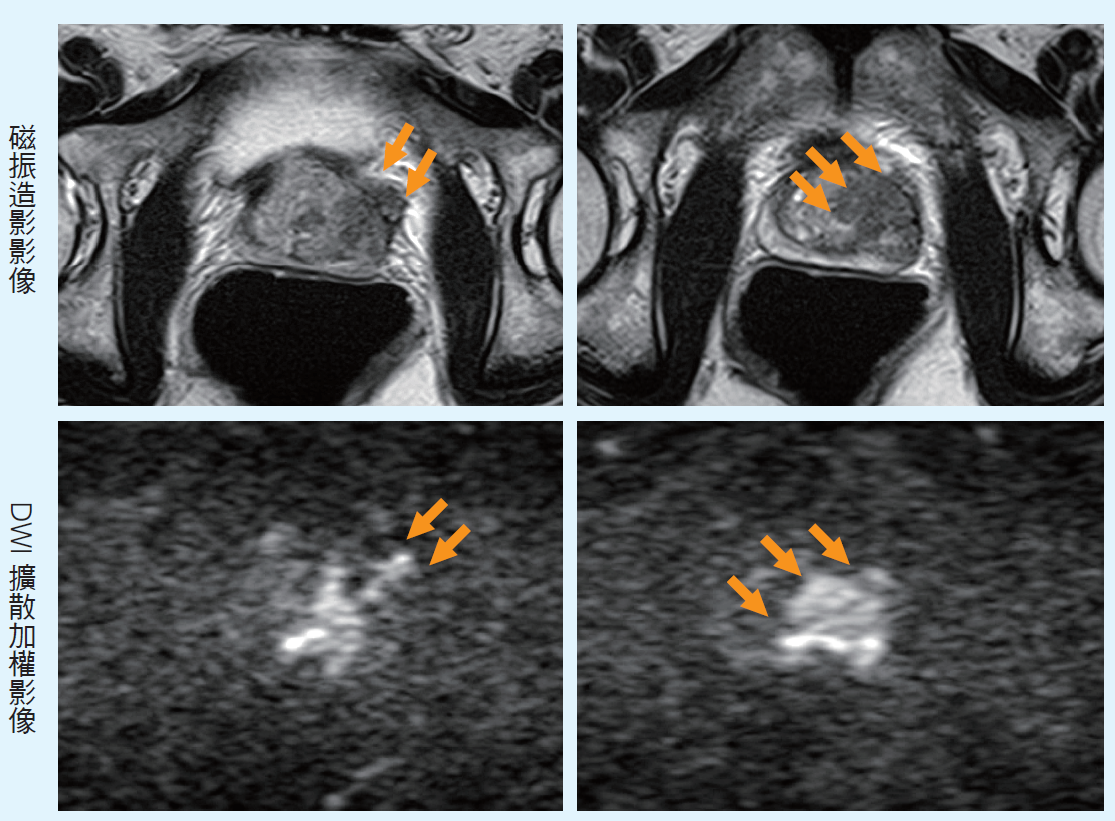

【案例二】

64歲男性,偶爾排尿不適,至泌尿科門診求診,醫師肛門指診攝護腺疑似硬塊,但PSA正常(0.93,正常值<4),患者無法決定是否進行切片檢查,醫師建議磁振造影檢查進一步評估。(上排)影像中,攝護腺有異常低訊號腫塊,已向外侵犯,範圍約3.5公分。(下排)病灶在DWI擴散加權影像中顯示異常高訊號。綜合以上影像特徵,經評分系統評估為5分,高度懷疑為攝護腺癌第三期。後經切片及手術確診攝護腺癌第三期。